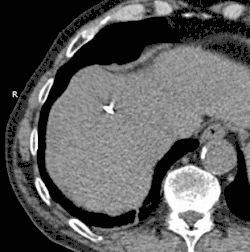

Description de cette image, également commentée ci-après

GIF animé montrant par scanner une cryoablation réalisée sur le foie. Le processus dure environ 30 minutes.